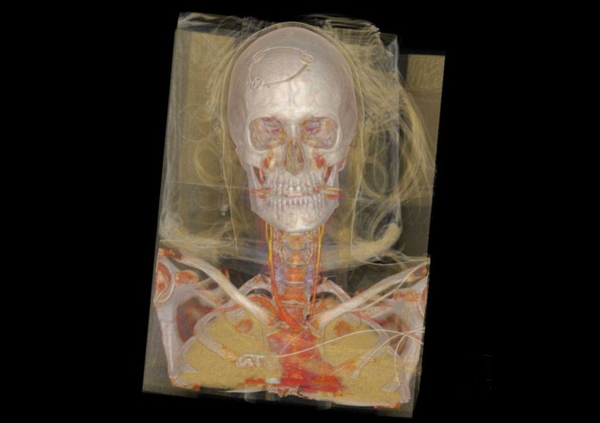

在随后的幻灯片中,您将看到来自瑞典医学图像科学与可视化中心(the Center for Medical ImageScience and Visualization ,CMIV)的Anders Persson和他的同事们运用CT,MRI和超声得到的令人惊叹的尸检图片。这些图片描绘了人体骨骼,消化道,循环系统和大脑以及野猪的前端结构。

7, 人体,正视;骨骼清晰可见。